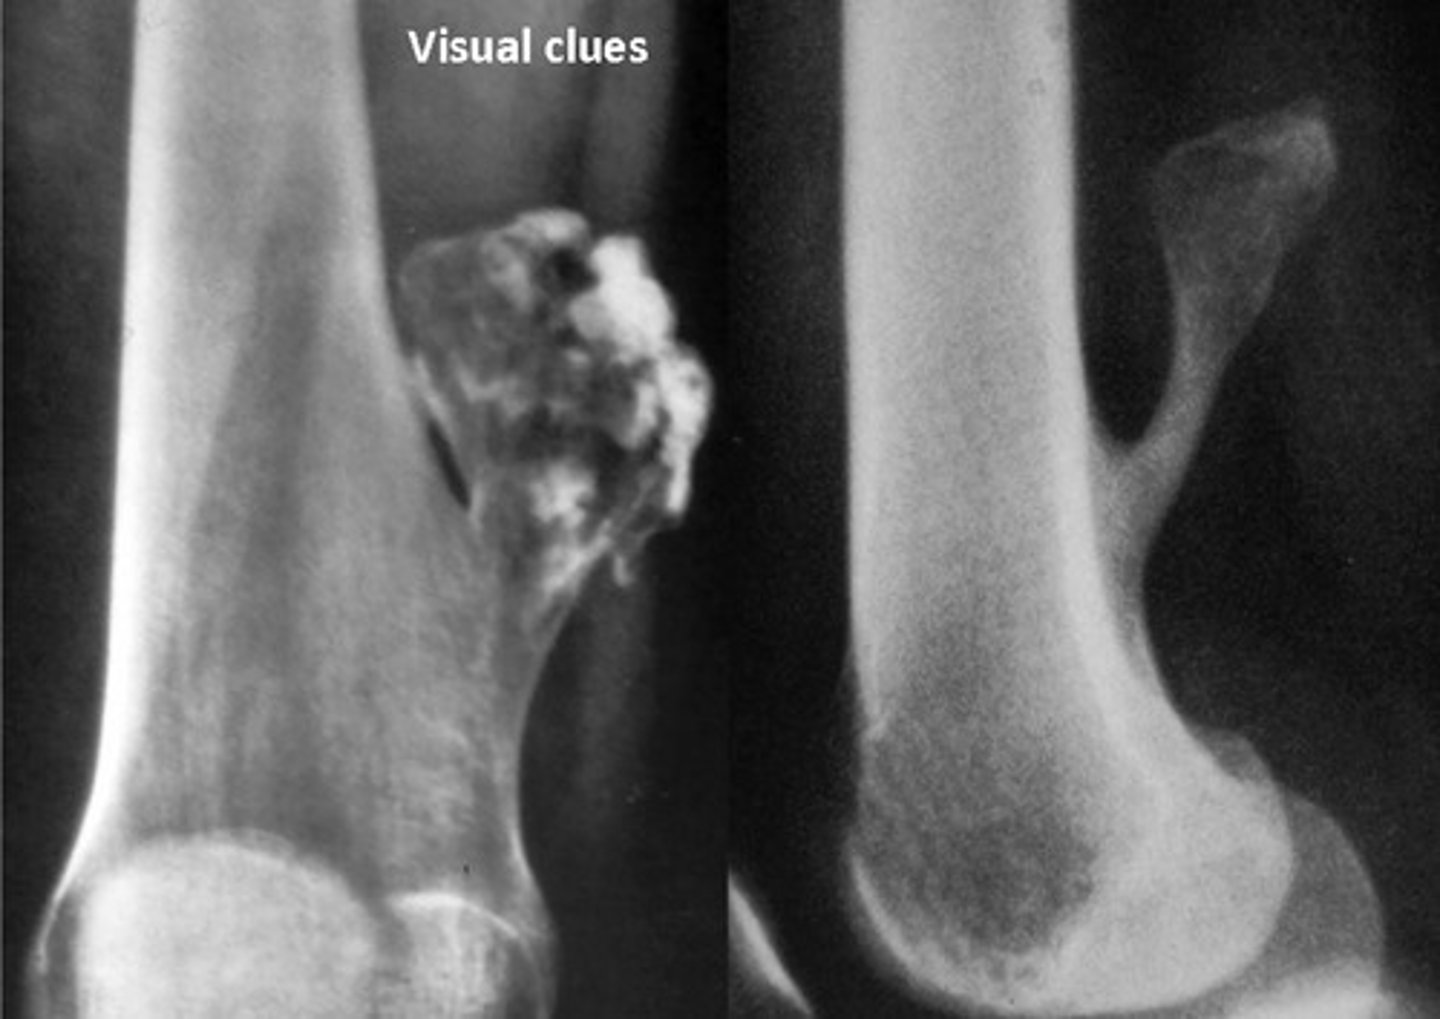

overall strcuture-image explain